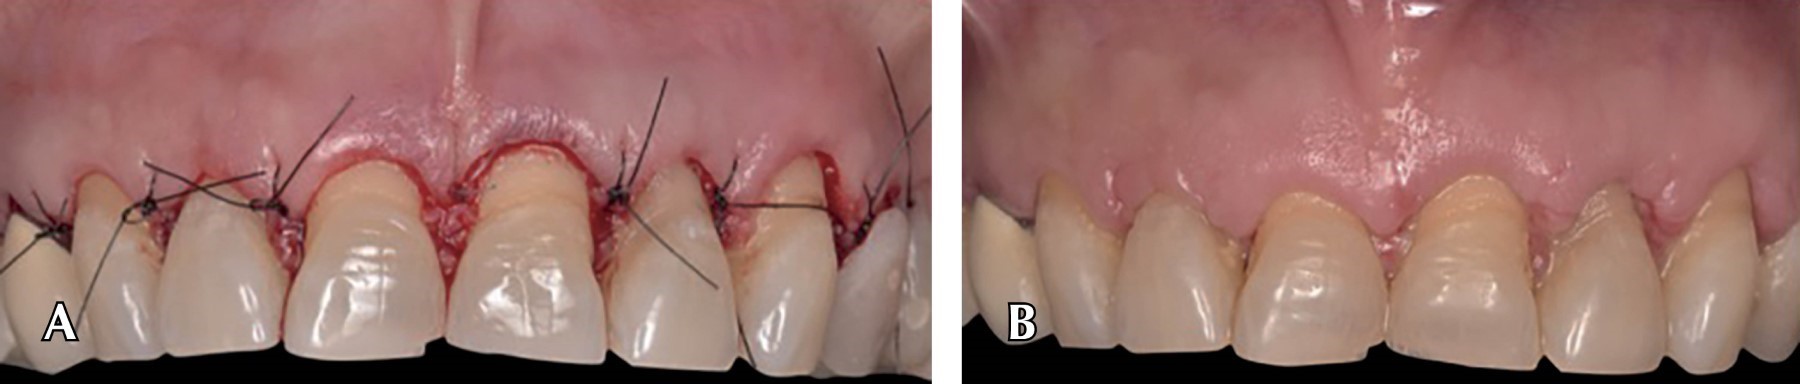

Introduction: the digital flow has reinvented processes in dentistry, from diagnostic methods to surgical protocols. The precision and brevity offered by digitalization has encouraged research and incorporation by the clinic to speed up time and reduce errors in dental treatments. The goal is to introduce even more digital flow in surgical procedures to reduce the operating time for the patient and the operator. Clinical case: a 70-year-old female patient, ASA I, referred by the Prosthodontics Department for crown lengthening in order to achieve compensation of the dentogingival tissues with the occlusal plane correction through the use of crown lengthening previously planned in EXOCAD. Pre and transoperative time was reduced, obtaining a more accurate symmetrical smile and gingival margin without compromising occlusion and periodontal tissues. Computer-aided design and manufacturing broadens the perspectives in a treatment plan, three diagnostic methods such as tomography, intraoral scanning and facial photographs are used together to perform a digital wax-up and articulator.

Figure 3